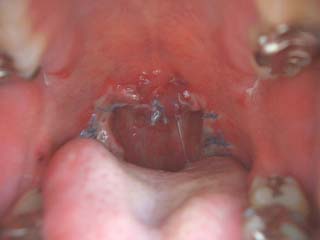

|

これが僕の扁桃腺。奥に二つ腫れてますねー

明日にはこいつともお別れです